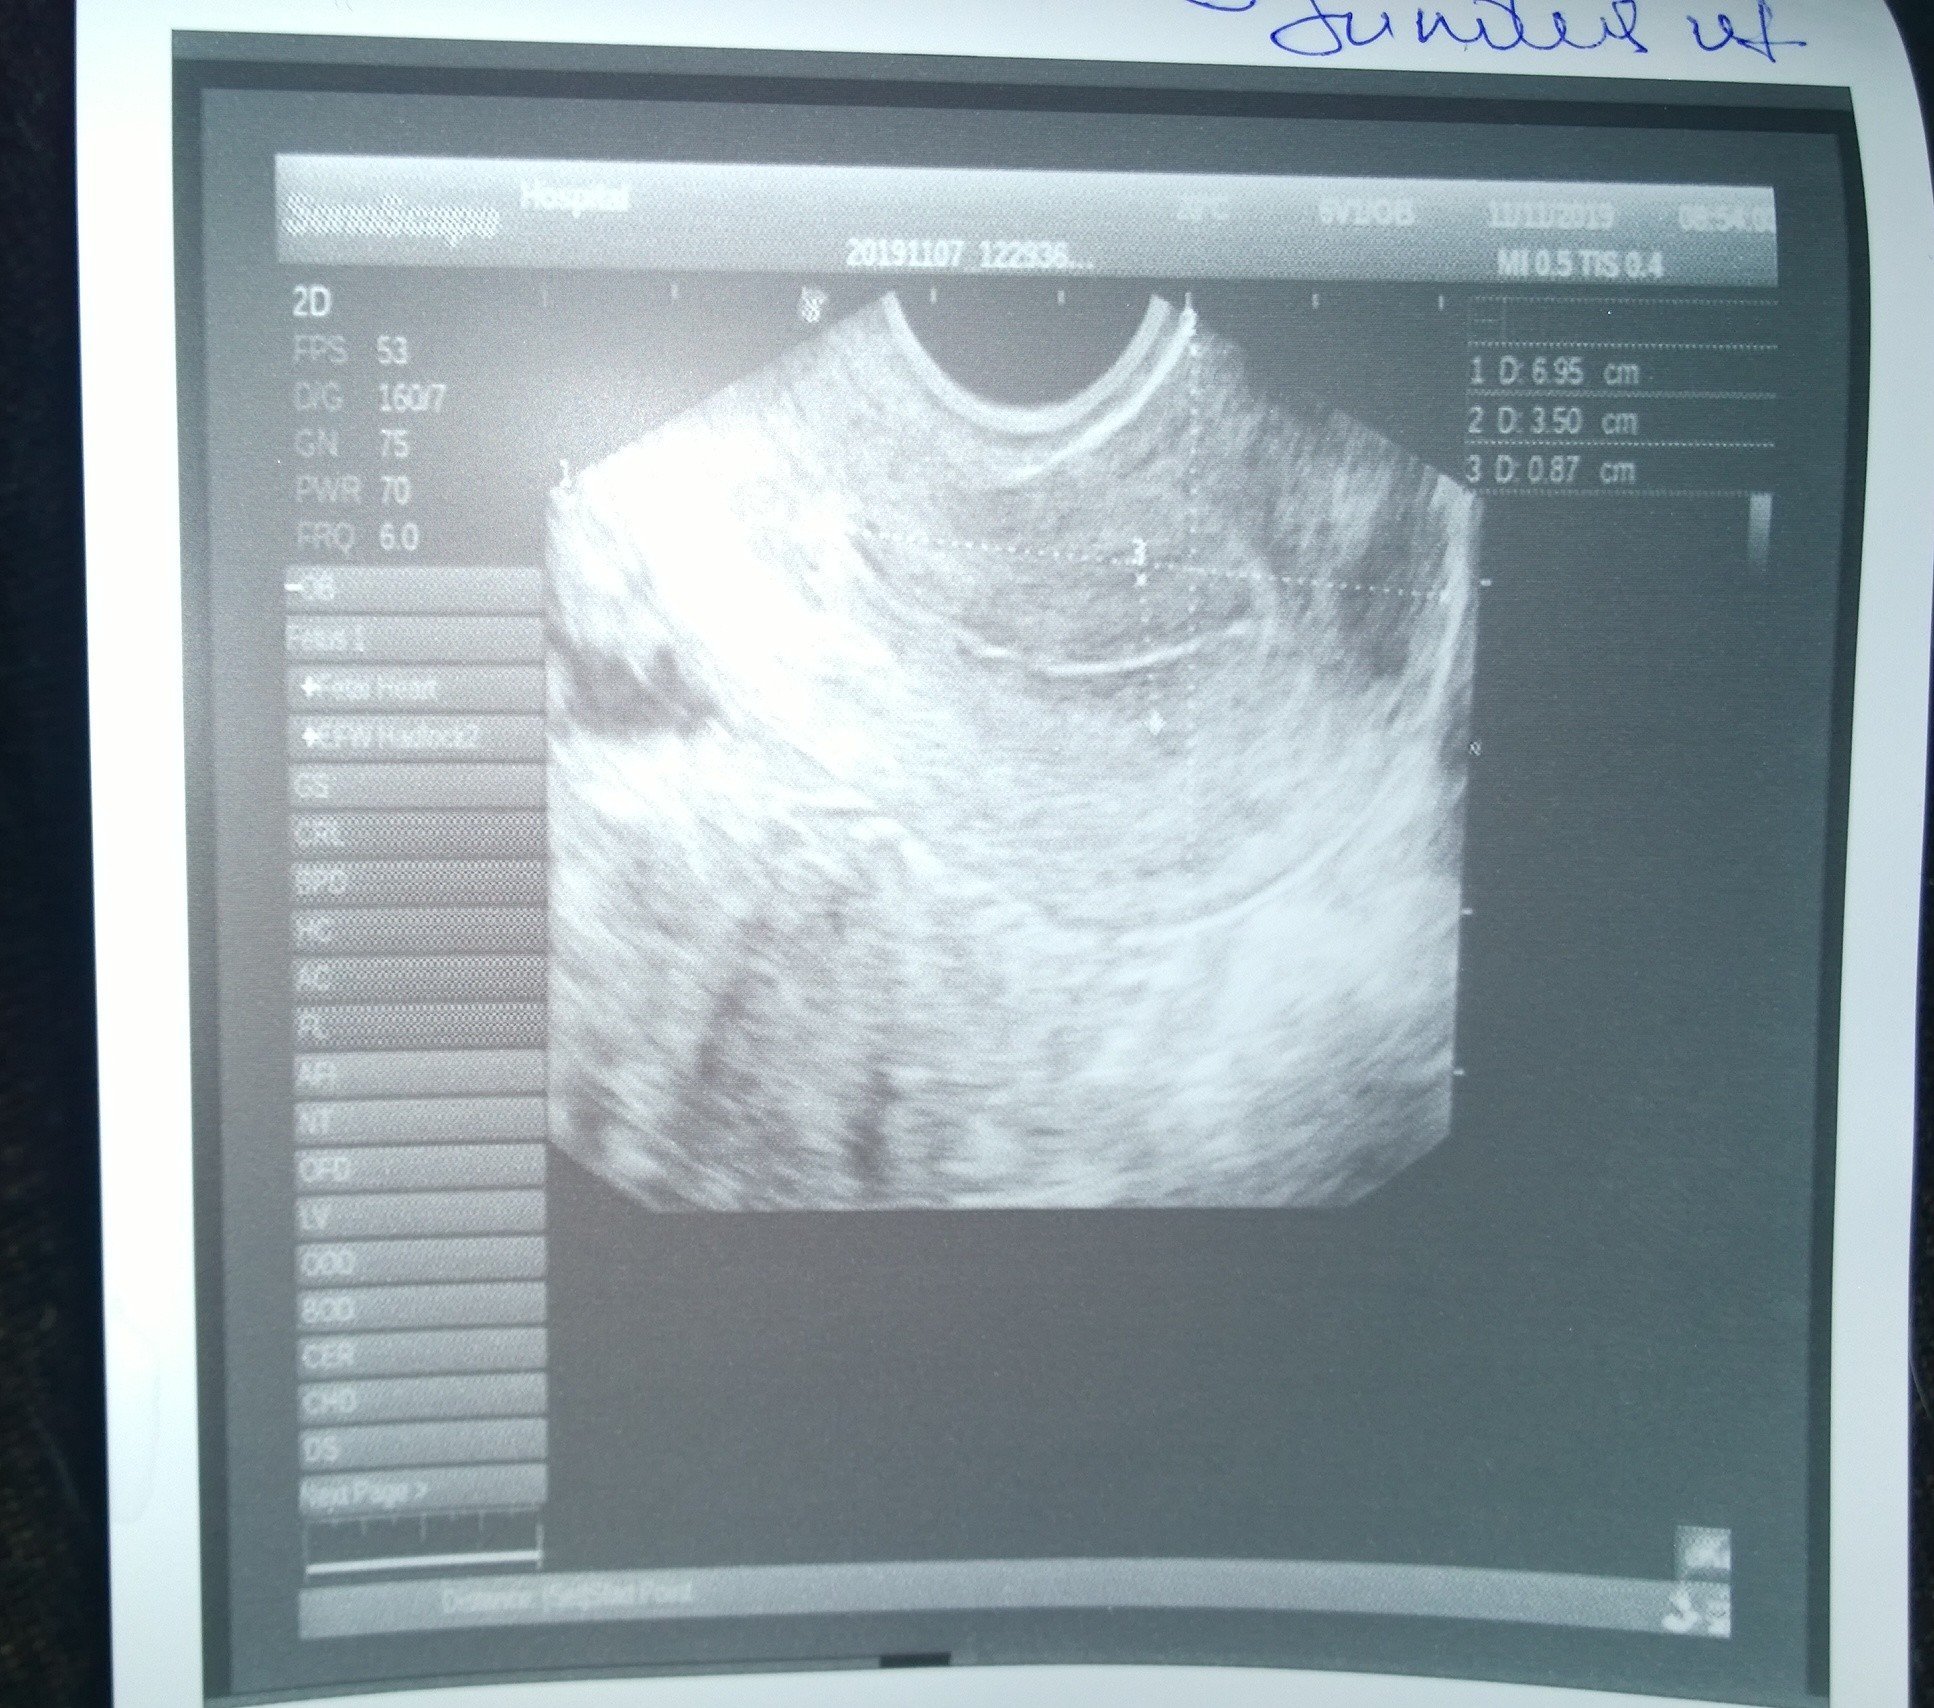

Хистероскопията е процедура, която включва директен оглед на маточната кухина с помощта на оптична система и осветление. Прилага се както за диагностични, така и за терапевтични цели при различни гинекологични състояния, като прекомерни или продължителни менструации, междуменструално кървене, нередовни менструални цикли, безплодие, съмнение за неправилно поставена вътрематочна спирала , съмнение за вродени маточни аномалии, съмнение за сраствания в маточната кухина и други. Хистероскопията е процедура, която включва използването на хистероскоп за изследване на вътрешността на матката. Извършва се с цел диагностициране и лечение на състояния като полипи, хиперплазия на ендометриума, рецидивиращи полипи и други проблеми, които могат да доведат до трудности при забременяване.